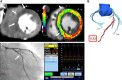

Myocardial ischemia is caused by a mismatch between myocardial oxygen consumption and oxygen delivery in coronary artery disease (CAD). Stratification and decision-making based on ischemia improves the prognosis in patients with CAD. Non-invasive tests used to evaluate myocardial ischemia include stress electrocardiography, echocardiography, single-photon emission computed tomography, and magnetic resonance imaging. Invasive fractional flow reserve is considered the reference standard for assessment of the hemodynamic significance of CAD. Computed tomography (CT) angiography has emerged as a first-line imaging modality for evaluation of CAD, particularly in the population at low to intermediate risk, because of its high negative predictive value; however, CT angiography does not provide information on the hemodynamic significance of stenosis, which lowers its specificity. Emerging techniques, e.g., CT perfusion and CT-fractional flow reserve, help to address this limitation of CT, by determining the hemodynamic significance of coronary artery stenosis. CT perfusion involves acquisition during the first pass of contrast medium through the myocardium following pharmacological stress. CT-fractional flow reserve uses computational fluid dynamics to model coronary flow, pressure, and resistance. In this article, we review these two functional CT techniques in the evaluation of myocardial ischemia, including their principles, technology, advantages, limitations, pitfalls, and the current evidence.